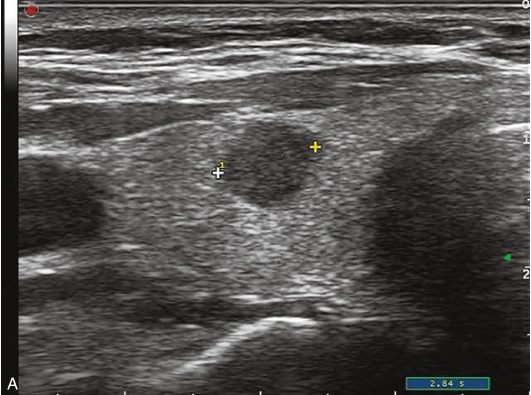

甲状腺右叶中部见一低回声结节,大小约2.0cm×0.9cm×1.7cm,部分边界不清楚,形态不规则,内可见多发点状强回声。CDFI结节内及周边可见较丰富血流信号,见图1-9-7。

图1-9-7 甲状腺髓样癌常规超声声像图

A.甲状腺右叶结节横切面;B.甲状腺右叶结节纵切面;C.甲状腺右叶结节CDFI血流图